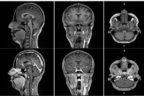

First-in-human contrast enhanced MRI images with GE HealthCare's mangaciclanol

First-in-human contrast enhanced MRI images with GE HealthCare’s mangaciclanol

MRI contrast agents enhance the visualization of abnormal structures or lesions during imaging procedures and help clinicians better distinguish between healthy and diseased tissue. Mangaciclanol is intended for general-purpose MR imaging and demonstrates comparable relaxivity (the ability to enhance signal intensity) to market-leading gadolinium-based agent, gadobutrol, with early clinical images suggesting similar diagnostic capability. Unlike gadolinium, which is a rare-earth metal, manganese is present in our food, and is an endogenous element, naturally occurring and autoregulated in the body. The macrocyclic ‘cage-like’ structure of mangaciclanol lessens the possibility of retention.

Phase 1 results for mangaciclanol showed the investigational agent was well tolerated in a first in human trial with no serious adverse events, no dose limiting toxicities, nor clinically relevant findings reported.